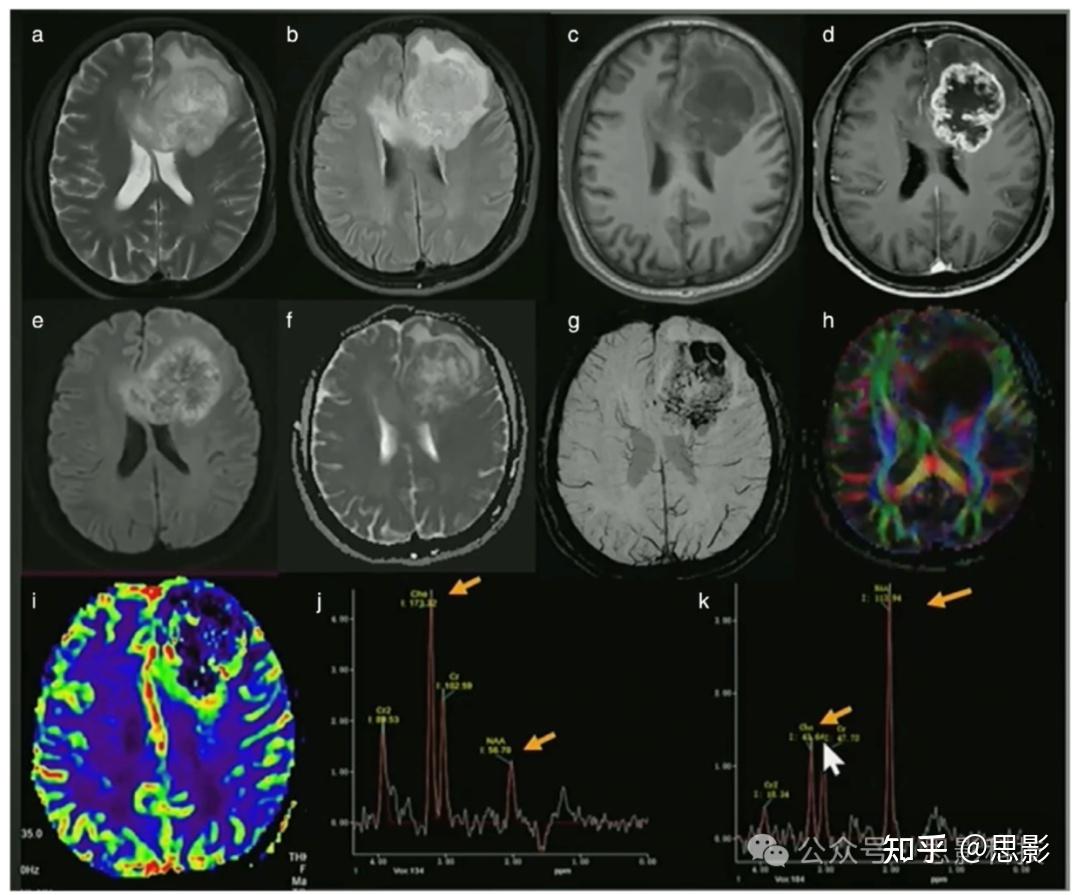

Roi 意思 影像 (99) 사진